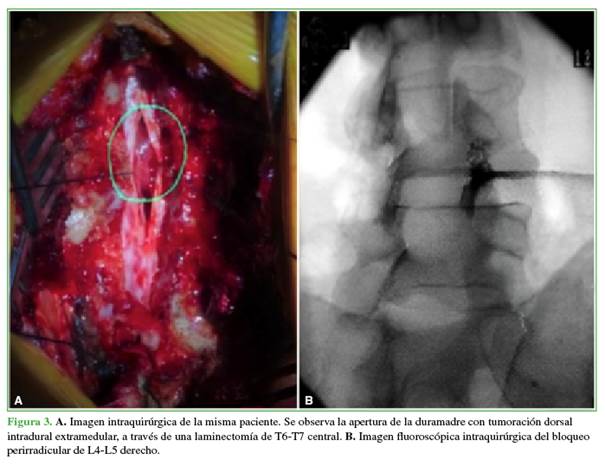

Una vez confirmado el diagnóstico de EETRS, tras cuatro días de hospitalización, se decidió realizar una descompresión de T6-T7 por vía posterior mediante laminectomía y exéresis del tumor intradural extramedular torácico, y un bloqueo intraquirúrgico derecho de L4-L5 (Figura 3).

La cirugía se llevó a cabo bajo anestesia general, con monitoreo intraoperatorio de potenciales evocados somatosensitivos y motores, y duró 2 h y 20 minutos. El análisis anatomopatológico reveló un meningioma transicional grado I de la OMS.9